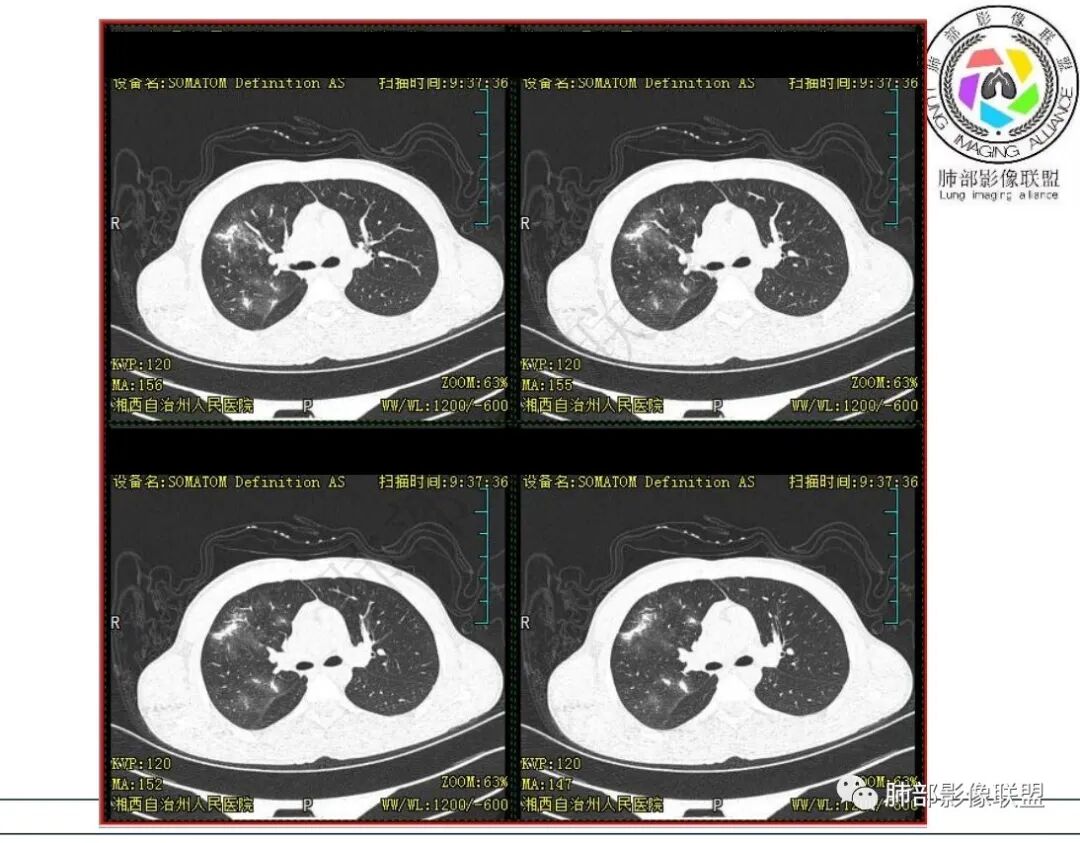

青少年,咳嗽伴咯血,右肺上叶多发结节状及片状高密度影,边缘模糊,部分可见空洞,呈薄壁,内壁光整,支气管管壁增厚、部分扩张,结核不支持,考虑NTM,鉴别真菌、金葡

青少年,病灶右肺上叶尖后段,多发空洞伴支扩,虽实验上无支持TB的依据,但结合临床考虑NTM可能性大,鉴别金葡

右肺上叶体积略缩小,大片状实变区,内有空洞影,内壁光滑,张力偏高,实变区内见充气支气管,病变周围多发片状磨玻璃影,界不清,多次送检未检测到结核杆菌,儿童,咳嗽,咳痰,咳血病史,考虑NTM

右肺多发斑片,结节,边界模糊,有晕,内见空洞,空洞壁光滑,气管壁增厚,考虑感染性病变,常规考虑结核,鉴别隐球菌,NTM。

男,15岁,咳嗽咳痰伴咯血盗汗10余天。既往有结核病患接触史。血沉增高,淋巴细胞稍低。胸部CT:右肺上叶多发实性斑片影、结节影、索条影,边界模糊,周围晕,边缘收缩,部分病灶内空洞,洞壁光滑。感觉病灶与血管关系密切。考虑:多发,多形态,空洞,血管炎?WG?鉴别TB、NTM、奴卡等慢性感染。